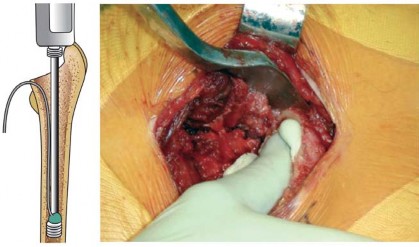

استبدال مفصل الورك الكلي بالإسمنت هو إجراء جراحي ناجح للغاية يعالج آلام الورك الشديدة ويستعيد وظيفة المفصل. يتضمن تثبيت غرسة الفخذ باستخدام إسمنت عظمي خاص، وتعتمد نتائجه الممتازة على دقة الخطوات الجراحية لضمان تثبيت قوي ومستقر يدوم طويلاً.

تقنية الإسمنت للفخذ، التي تُعد محور حديثنا، هي طريقة راسخة لتثبيت المكون الفخذي (الجزء الذي يتم إدخاله في عظم الفخذ) من المفصل الصناعي باستخدام إسمنت عظمي خاص. يضمن هذا الإسمنت استقرارًا فوريًا وقوة تحمل عالية، مما يجعله خيارًا ممتازًا للعديد من المرضى، وخاصة كبار السن وذوي العظام الضعيفة. ستكتشف في هذا الدليل لماذا تُعد هذه التقنية خيارًا موثوقًا به، وكيف يمكن أن تُحدث فرقًا حقيقيًا في حياتك.